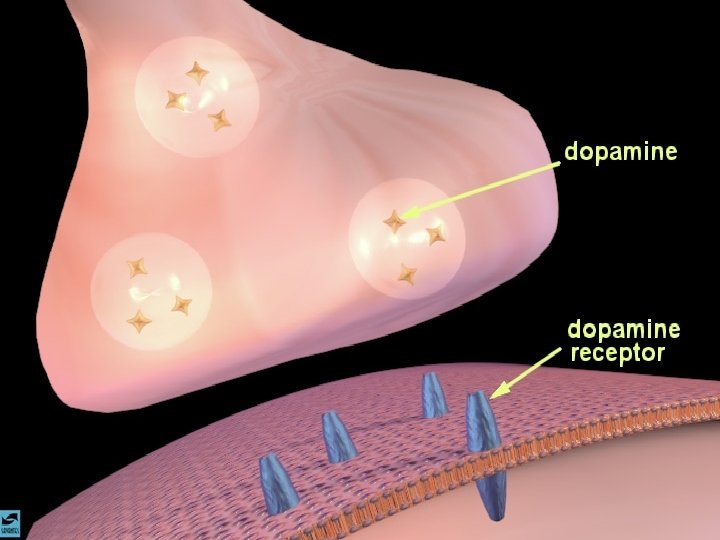

A AÇÃO DAS DROGAS NO SISTEMA NERVOSO CENTRAL A SINAPSE

A AÇÃO DAS DROGAS NO SISTEMA NERVOSO CENTRAL OS NEUROTRANSMISSORES - NORADRENALINA - SEROTONINA - DOPAMINA - GABA - ACETILCOLINA

ANFETAMINAS E COCAÍNA EFEITOS CEREBRAIS: ATIVA OS SISTEMAS DOPAMINÉRGOS MESOLÍMBICOS E MESOCORTICAIS, INIBINDO A RECAPTAÇÃO DE DOPAMINA NOS TERMINAIS SINÁPTICOS E PROMOVENDO SUA LIBERAÇÃO NAS SINAPSES.

OS OPIÁCIOS EFEITOS CEREBRAIS OS OPIÁCIOS LIGAM-SE AOS RECEPTORES CEREBRAIS DE ENDORFINAS